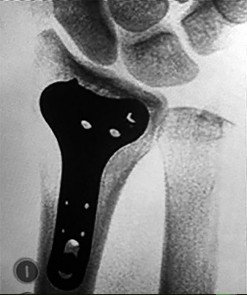

- الأشعة السينية (X-rays): هي الخطوة الأولى في تقييم الكسور، الخلوع، وتغيرات التهاب المفاصل. تساعد في تحديد مدى تدهور العظام والمسافات المفصلية. على سبيل المثال، تُظهر صور الأشعة السينية كسور السلاميات

أو كسور قاعدة العظم المشطي الخامس

، بالإضافة إلى علامات مثل "الدمعة الشعاعية" (Radiographic Teardrop) في الرسغ التي تمثل الزاوية الزندية الراحية الحرجة للكعبرة البعيدة

. - الأشعة المقطعية (CT Scan): توفر صوراً تفصيلية ثلاثية الأبعاد للعظام، وهي مفيدة جداً لتقييم الكسور المعقدة، مثل كسور العظم الخطافي (Hamate Hook Fracture) التي قد لا تظهر في الأشعة السينية العادية